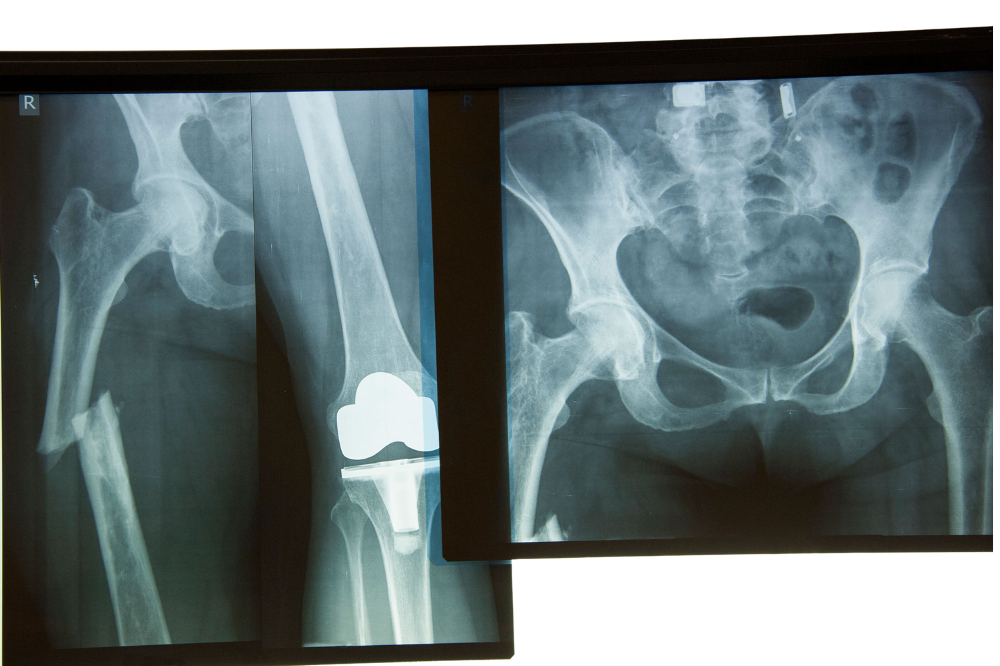

🥈 第2位:股関節の骨折(大腿骨近位部骨折)

「骨折くらい、治ればまた歩ける」と思っていませんか? 実はここに大きな落とし穴があります。

股関節の骨折は安静にして治すのが困難です。

高齢者がじっと安静にするだけでも、筋肉が著しく落ちて歩けなくなり、肺炎や床ずれができる危険も出てきます。

A. 股関節の骨折のほとんどは「転倒」が原因です。

そして転んで骨が折れてしまうのは「骨粗鬆症」で骨がスカスカになっているからです。